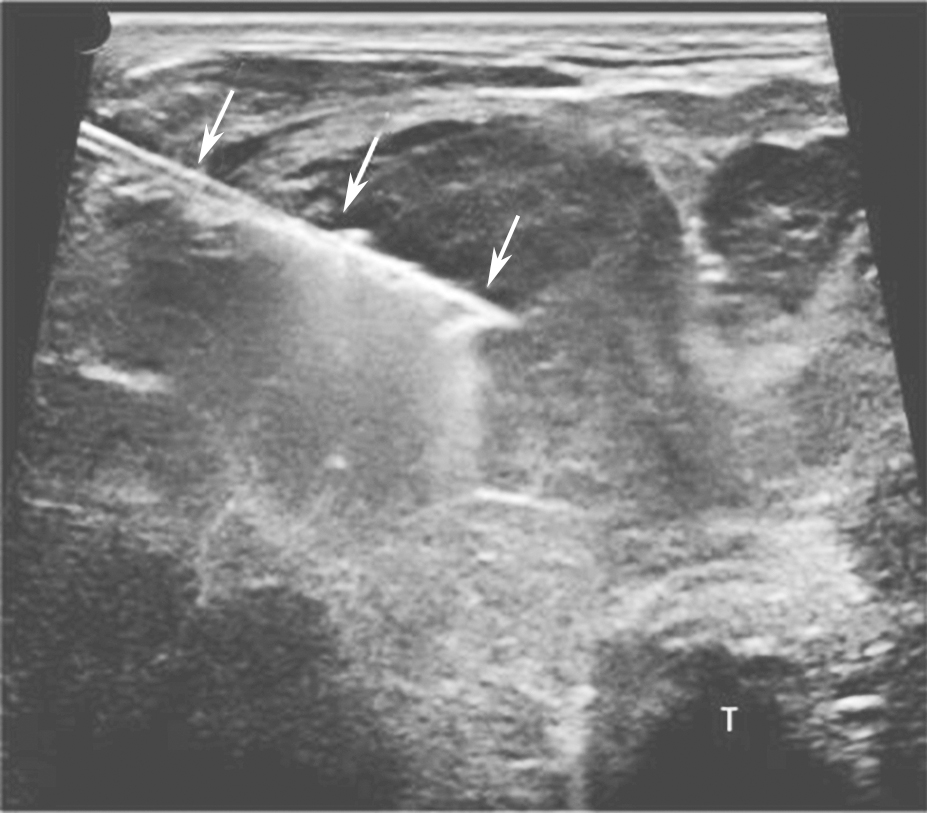

桥本甲状腺炎超声表现为甲状腺弥漫性增大,以前后径改变最为明显,峡部明显增厚。腺体包膜清晰完整,回声弥漫性不均减低(图2)。腺体内可见多个由淋巴组织、残余滤泡和上皮组织形成的无占位效应的低回声小结节。腺体广泛纤维化后体积可缩小。甲状腺下极附近淋巴结增大对于诊断有参考价值。

图2颈部正中横切面:甲状腺腺体回声不均匀,峡部增厚,可见多个无占位效应的低回声小结节(箭头所示),T:气管